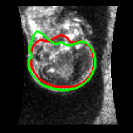

To quantitatively compare our network to the only other brain extraction method for fetal 3D US, the out test dataset was analysed with the method described in Namburete et al., 2018 [8]. The same experiments were performed and the results are shown in Table 3. Our network manages considerably better results throughout all comparisons. This is expected, since the other method relies on an approximation of the brain volume as ellipsoid, which does not accurately represent its shape. While an ellipsoid would be expected to have a high SC, its fitting to the probability mask results in an inaccurate alignment, which is reflected in the low SC of 0.74, compared to our network’s 0.95. This can be clearly seen in Fig. 7, where a comparison of their method with ours is shown.

| Original | Namb. 01 | Namb. 02 | Our work |